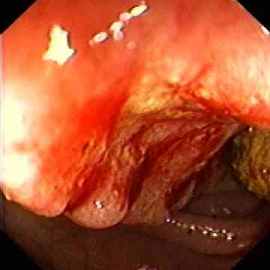

Oesophagus:A typical oesophageal cancer